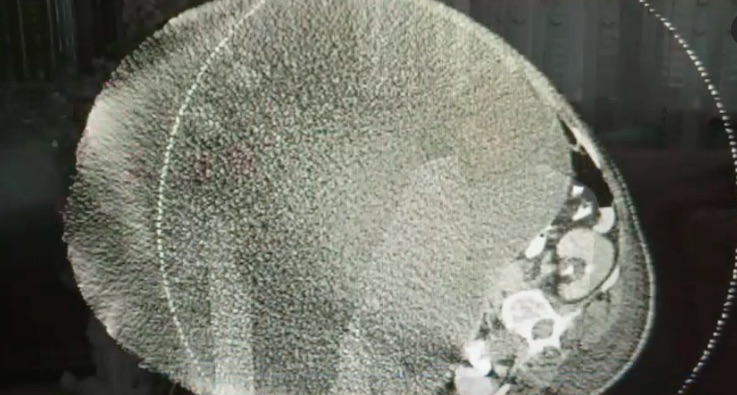

Hẳn mọi người sẽ lấy làm ngạc nhiên bởi trong 1 ngày mà giảm được 100kg? Nhưng đúng như vậy, bà Mary Clancey sống tại Pennsylvania (Mỹ) vừa được giải phóng khỏi khối u quá khổ. Nó đă hành hạ cơ thể của bà hơn 16 năm trời.

Khối u nặng hơn 60kg

Tới tháng 11.2016, bà bị tắc mạch máu ở chân. Khi phải điều trị, bệnh viện mới phát hiện lư do khiến bà tăng cân, đó là một khối u khổng lồ ở một bên buồng trứng. Clancey quá sốc khi được thông báo kết quả xét nghiệm.

Ngay sau đó, bác sĩ đă thực hiện mổ tách khối u nặng 63kg cùng 30kg da thừa. Trong những ngày hậu phẫu, Clancey cảm thấy khá kỳ lạ khi có thân h́nh c̣ hương chỉ trong 1 ngày.